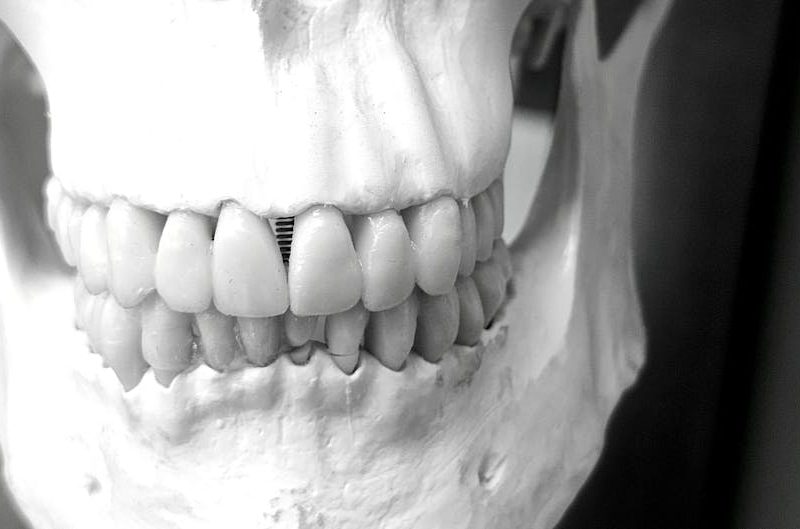

Corachán Maxilofacial